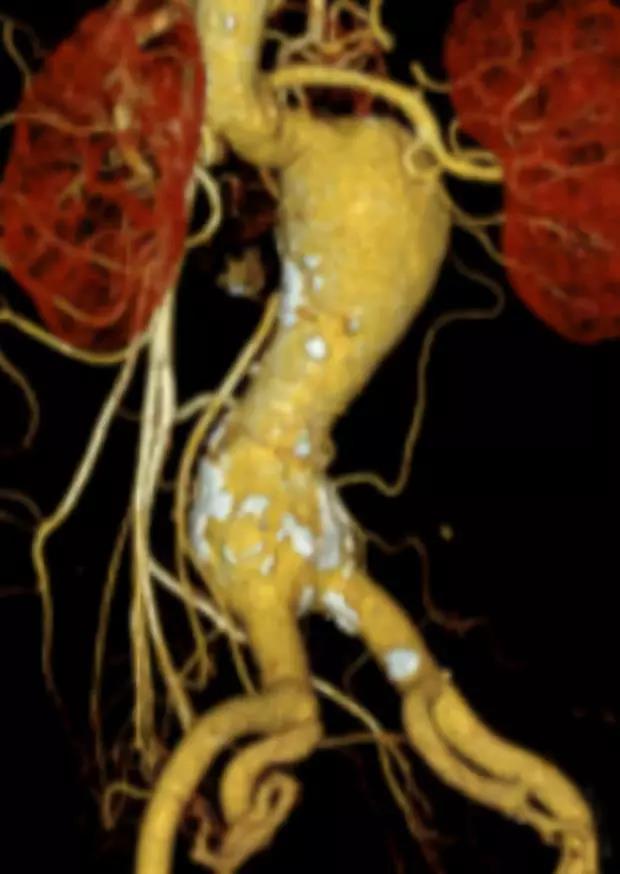

此次研究,纳入腹主动脉瘤的最大直径为85mm,平均直径为50.78mm;最短瘤颈长度为11mm,平均长度为31.34mm;最大肾下成角为74.6度,平均角度为32.48度。从动脉瘤最大直径变化来看,经过腹主动脉腔内治疗后,在出院前和术后6个月都有所减小。 在此次研究中,彩神在线网信彩票-彩神通免费版下载-彩神8争霸vlll-彩神购彩购彩大厅-彩神软件陆立根免费版-彩神ll争霸3-彩神ll彩神8-彩神ll争霸彩票-拼搏在线彩神网网页版Yuranos™新一代腹主动脉覆膜支架系统临床试验初步展现了优秀的临床试验结果,其30天内MAE发生率低,安全性得以验证;而且由于该产品的柔顺性有较大提升,输送器直径减小,对于短瘤颈和角度大的病例是更好的选择。 入组病例展示: 病例一:男性,年龄69岁,既往高血压,糖尿病病史。术前腹主动脉瘤直径67.3mm,近端瘤颈长度23.2mm,近端锚定区直径21.2mm,肾下成角60.5度。 术中从右侧股动脉穿刺,选用彩神在线网信彩票-彩神通免费版下载-彩神8争霸vlll-彩神购彩购彩大厅-彩神软件陆立根免费版-彩神ll争霸3-彩神ll彩神8-彩神ll争霸彩票-拼搏在线彩神网网页版型号为AB-2412-50-120的主体支架,支架近端定位于右肾动脉开口处,后释放打开裸支架,并向下释放主体短分支,左侧输送进入彩神在线网信彩票-彩神通免费版下载-彩神8争霸vlll-彩神购彩购彩大厅-彩神软件陆立根免费版-彩神ll争霸3-彩神ll彩神8-彩神ll争霸彩票-拼搏在线彩神网网页版髂动脉延长支架IE-1416-100,并释放,保留左侧髂内动脉。接着释放主体长分支,右侧输送进入彩神在线网信彩票-彩神通免费版下载-彩神8争霸vlll-彩神购彩购彩大厅-彩神软件陆立根免费版-彩神ll争霸3-彩神ll彩神8-彩神ll争霸彩票-拼搏在线彩神网网页版髂动脉延长支架IE-1424-80,并释放,保留右侧髂内动脉。 手术顺利,无内漏,持续时间1小时10分钟。术后CTA检查,支架形态良好,无内漏。详见下图: 术前影像 术中影像 出院前影像 术后6个月影像 术后1年影像 病例二:女性,年龄72岁,既往高血压,静脉曲张病史。术前腹主动脉瘤直径48.81mm,近端瘤颈长度16.15mm,近端锚定区直径18.43mm,肾下成角66度。 术中从右侧股动脉穿刺,选用彩神在线网信彩票-彩神通免费版下载-彩神8争霸vlll-彩神购彩购彩大厅-彩神软件陆立根免费版-彩神ll争霸3-彩神ll彩神8-彩神ll争霸彩票-拼搏在线彩神网网页版型号为AB-2412-50-140的主体支架,支架近端定位于右肾动脉开口处,后释放打开裸支架,并向下释放主体短分支,左侧输送进入彩神在线网信彩票-彩神通免费版下载-彩神8争霸vlll-彩神购彩购彩大厅-彩神软件陆立根免费版-彩神ll争霸3-彩神ll彩神8-彩神ll争霸彩票-拼搏在线彩神网网页版髂动脉延长支架IE-1414-120,并释放,保留左侧髂内动脉。接着释放主体长分支,右侧输送进入彩神在线网信彩票-彩神通免费版下载-彩神8争霸vlll-彩神购彩购彩大厅-彩神软件陆立根免费版-彩神ll争霸3-彩神ll彩神8-彩神ll争霸彩票-拼搏在线彩神网网页版髂动脉延长支架IE-1414-80,并释放,保留右侧髂内动脉。

手术顺利,无内漏,持续时间1小时10分钟。术后CTA检查,支架形态良好,无内漏。详见下图: